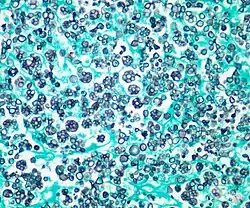

| Histologic stain of a Prototheca zopfii infection in a dog | |